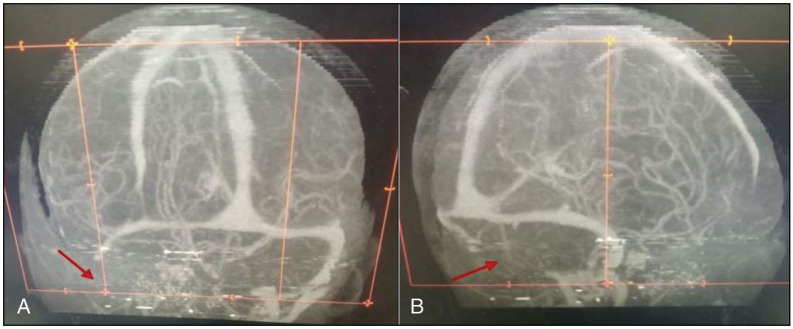

脑静脉窦血栓形成(CVST)是一种罕见且未被报道的神经系统疾病。这种情况有多种病因、临床表现,如果不及时治疗,会有明显的后遗症。我们报告的情况下,一个10岁的男性发烧,改变感觉,颅神经病变,和左偏瘫。他的影像学表现与CVST一致,随后入院时发现他的直肠有活蠕虫。他接受了非手术治疗,病情明显好转,出院时伴有残余运动障碍。此外,我们对已发表的CVST合并蛔虫病的病例报告进行了文献回顾,强调了其可能的病理生理、临床谱和管理特点。

Cerebral venous sinus thrombosis (CVST) is an uncommon and underreported neurological condition. This condition has varied aetiologies, clinical manifestations, and significant sequelae if left untreated. We report the case of a 10-year-old male with fever, altered sensorium, cranial nerve neuropathies, and left hemiplegia. His imaging findings revealed features consistent with CVST, and he was subsequently noticed to be passing live worms per rectum while on admission. He was managed nonoperatively, improved significantly, and was discharged with residual motor deficits. In addition, we present a literature review of published case reports of CVST associated with helminthiasis, highlighting its possible pathophysiology, clinical spectrum, and management peculiarities.